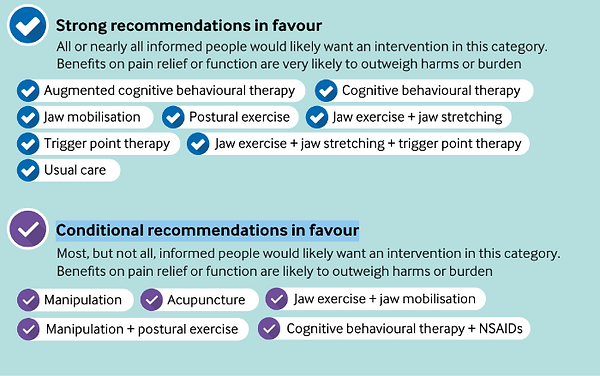

Les dernières recommandations publiées dans le BMJ (British Medical Journal) en décembre 2023

Fortes recommandations en faveur :

- Thérapie comportementale et cognitive (TCC)

- Mobilisations passives de l'articulation

- Exercices de posture

- Exercices et étirements des muscles de l'articulation ATM

- Traitements des points gâchettes (trigger points therapy)

- Soins habituels

Recommandations en faveur sous conditions :

- Manipulation

- Anti-inflammatoires non stéroïdiens + TCC

- Acupuncture

- Exercices + mobilisations de l'articulation

Les deux approches sont complémentaires. Le dentiste traite les composantes occlusales (gouttière, ajustement dentaire). L'ostéopathe agit sur les composantes musculaires et articulaires. Une prise en charge coordonnée est recommandée par les experts selon les recommandations BMJ 2023.